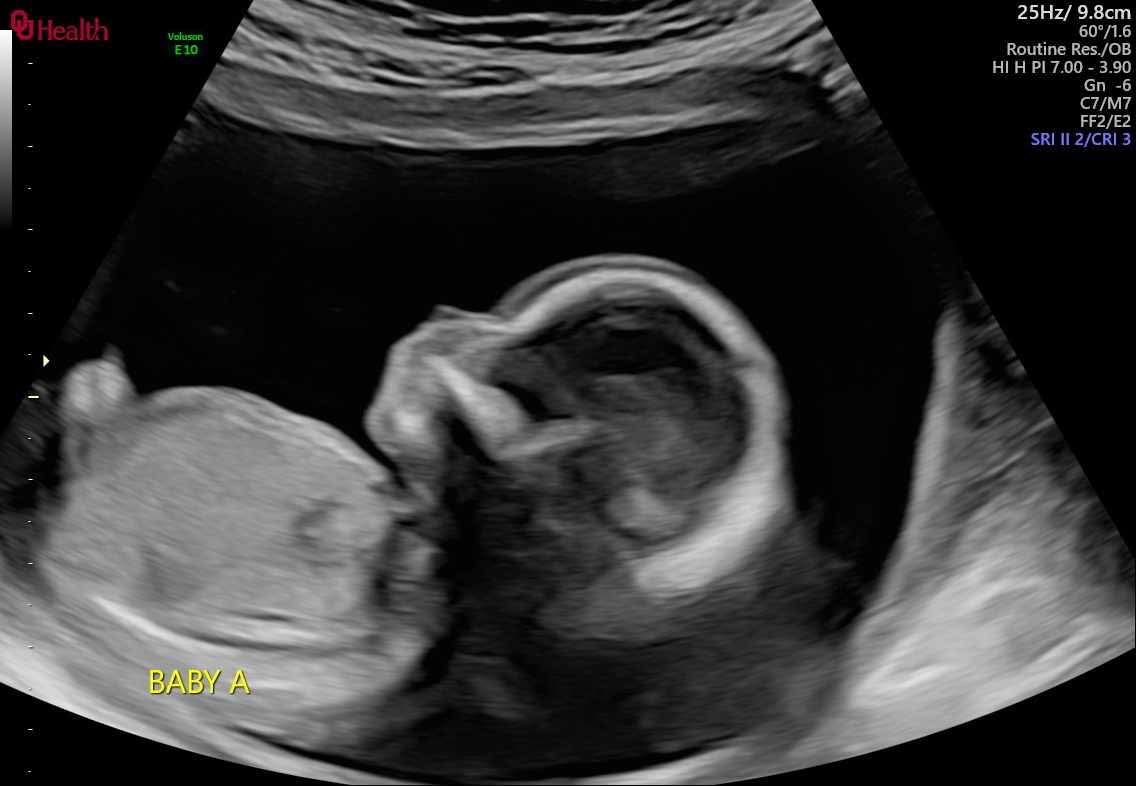

On Wednesday, July 9th 2025 my sister Carmen was rushed into the operating room due to heavy bleeding though she was already being monitored for it for weeks , they had diagnosed her with placenta previa with accreta with this pregnancy. The twins are considered monozygotic twins( high risk) because they shared the same placenta but different sac. Around 5:13am I received a texted message that she had delivered her babies and had received a total of 4 blood transfusions due to the large amount of blood loss which resulted in needing a full hysterectomy.. Baby A has a hear condition called hypoplastic left heart syndrome and will need multiple operations in the future ; however they were born at just 28weeks gestation making it difficult for those surgeries. Baby B had Acrania , polyhydraminas and passed away 1 hour after being born.. he was held and loved deerly by dad and family members but unfortunately my sister was not able to hold him while he was alive. We are asking for prayers, and any help for medical expenses for my sister and funeral expenses for baby Luis Ojeda. Prayers are highly appreciated especially for baby A , Michael Jr Ojeda to receive healing in Jesus name! My sister Carmen and Michael appreciate it very much! Thank you so much for any help with lots of love ❤️